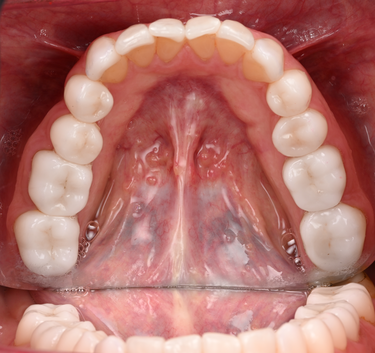

For this case, the patient was confident about her choice of having a BL4 bleach shade - bright but natural-looking teeth, therefore focus shifted to reproducting the milti-layered effects of a natural tooth after considering the BL selection of ingots (Figs. 1-2).

Figure 1: Inital Situation